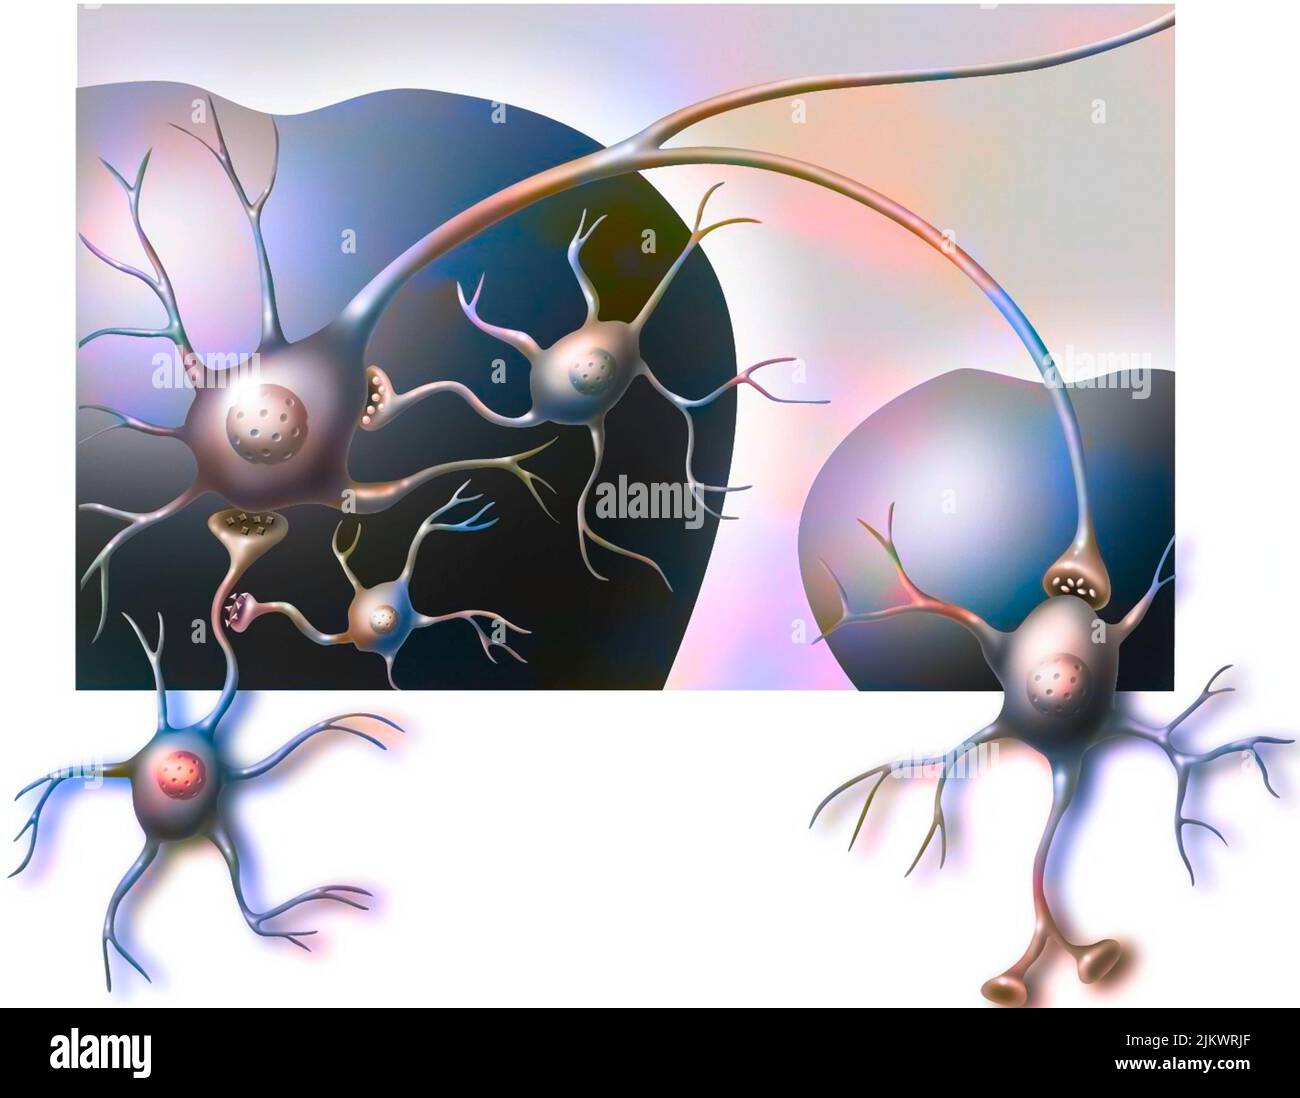

RF2JKWRF2–Pla (potentialisation à long terme) après une semaine, étape 2 : la synapse est stimulée avec une plus grande efficacité.

RF2JKWR03–Action des sels minéraux et des vitamines sur la transmission des impulsions nerveuses aux synapses.